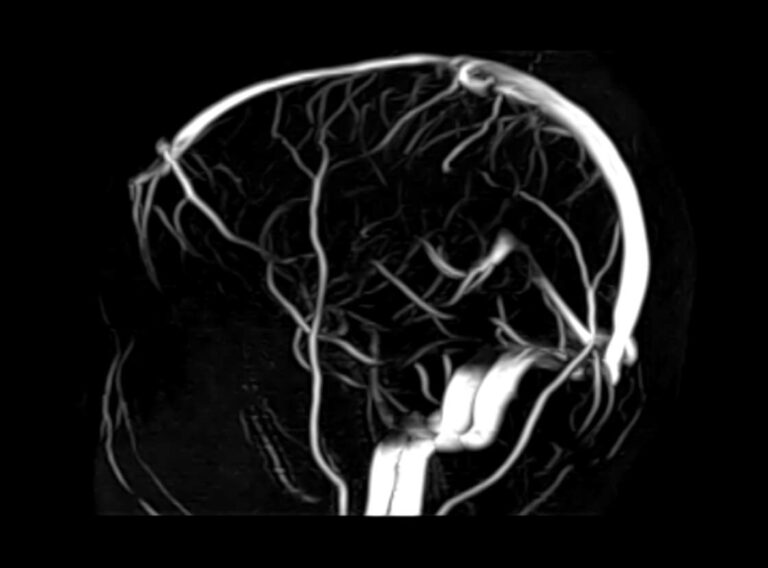

Стандартная МРТ головного мозга дает важную информацию о состоянии и структуре мозговой ткани для выявления большого числа заболеваний, в том числе опухолевых образований, демиелинизирующих заболеваний, воспалительных процессов головного мозга и мозговых оболочек. Стандартную МРТ головного мозга дополняет МР-ангиография, которая отображает состояние артериальной системы кровоснабжения головного мозга. МР-венография головного мозга позволяет детально изучить особенности анатомического и функциональной состояния венозного русла головного мозга.

Компьютерная программа обрабатывает данные, полученные при сканировании, и формирует объемные изображения как самого мозга, так и сосудистой системы в отдельности без прилегающих тканей. Обе методики применяются одновременно и взаимодополняют друг друга, давая полную диагностическую картину.